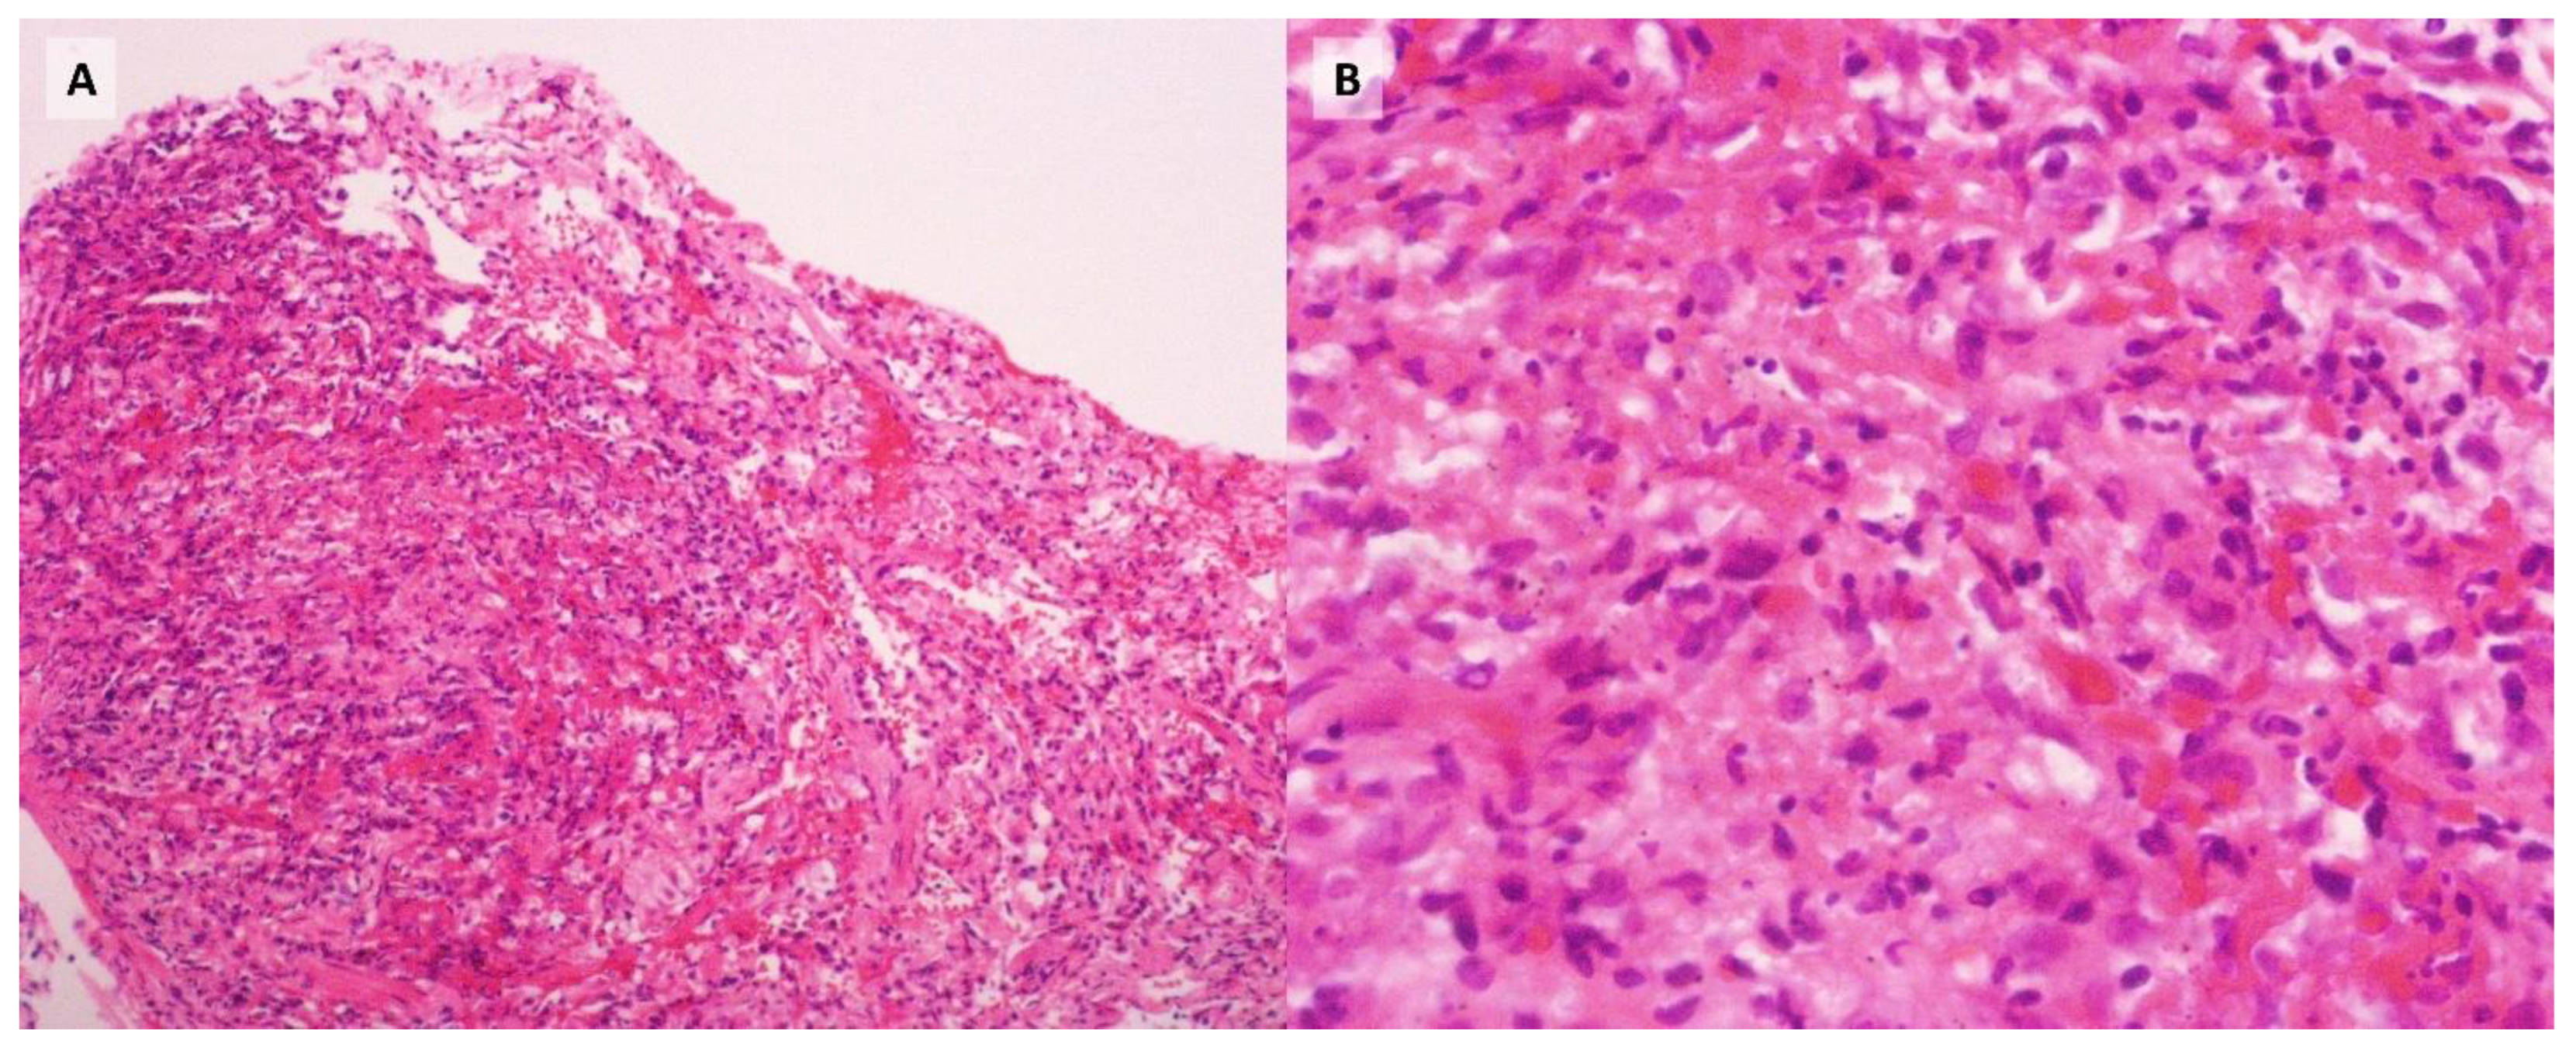

Despite targeted therapy, the patient experienced progressive clinical deterioration, ultimately developing respiratory failure that required orotracheal intubation and admission to the intensive care unit (ICU) on day 10 of hospitalization. By day 12, the report was received. Subsequent transbronchial biopsies were positive for Pneumocystis jirovecii and fungi morphologically consistent with Histoplasma (Figure 2, Figure 3), with no other infectious agents detected in the BAL samples or the blood and bone marrow cultures. Consequently, antifungal therapy was adjusted to include liposomal amphotericin B (5 mg/kg/day) and itraconazole (200 mg tid). However, despite intensive therapeutic interventions, the patient's condition continued to worsen, culminating in a fatal outcome on day 31 of her hospitalization.

Furthermore, Pneumocystis is particularly challenging to culture, with detection primarily relying on PCR testing or direct visualization in induced sputum or bronchoalveolar lavage (BAL) samples.[3] In contrast, Histoplasma can be isolated, but the sensitivity of respiratory samples typically ranges from 0% to 60%. It is important to note that blood cultures and bone marrow cultures demonstrate higher sensitivity, ranging from 60% to 90%. However, fungal cultures require extended periods for growth (2-3 weeks), making PCR studies a valuable alternative, as they provide rapid results with a sensitivity ranging from 67% to 100%.[10] Unfortunately, our institution lacks the capability to perform PCR testing for fungal infections. In our case fungal cultures were negative, and histoplasmosis was only detected in biopsy samples, not in the BAL. This delay in diagnosis hindered the timely initiation of targeted antifungal therapy. As diagnostic methods, such as PCR for fungal infections, become more widely available, it is likely that more cases of co-infection, such as the one presented, will be identified.

Figure 3. Grocott's methenamine silver stain, 100X magnification. (A) Yeast-like fungi with morphology consistent with Histoplasma capsulatum in transbronchial biopsy. (B) Fungi with morphology consistent with Pneumocystis jirovecii in bronchoalveolar lavage.